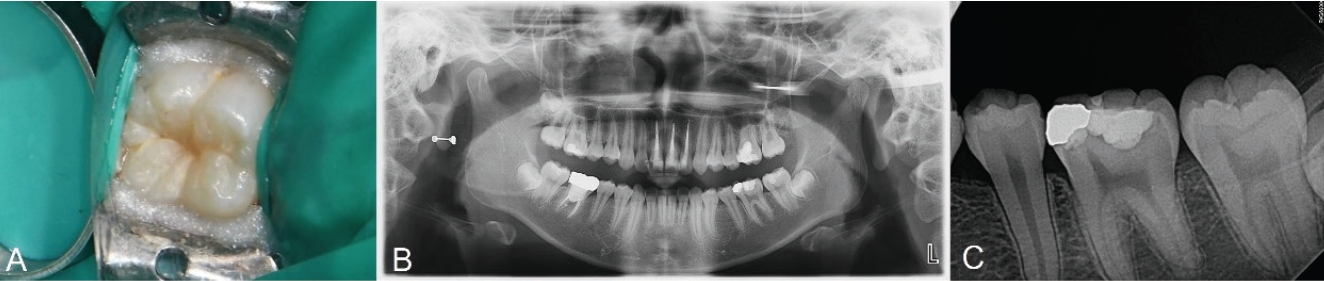

14세 남성 환자가 부산대학교치과병원 치과보존과에 좌측 하악 구치부 우식을 주소로 내원하였다. 환자의 전신 병력 및 치과 병력 특이사항은 없었다. 구내 검사에서는 좌측 하악 제2대구치에서 치면열구 우식이 관찰되었다. 교합면 형태는 보존되어 있었고, 명확한 공동(cavitation)은 관찰되지 않았다(Fig. 1A). 냉자극과 온자극에 대한 반응은 정상적이었다. 타진이나 저작에 대한 통증도 없었다. 파노라마 및 구내치근단방사선 상 상아질까지 진행된 깊은 우식을 관찰할 수 있었다(Figs. 1B and C). 이 결과를 바탕으로 우식 부위를 복합레진으로 수복하면서 스탬프 테크닉을 적용하기로 결정하였다.

Initial examination radiograph and clinical photograph. A. No loss of tooth structure is observed. B. Pre-operative radiograph. C. Caries of dentin is seen on olwer left second molar.